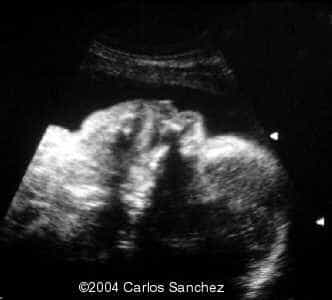

Antenatal scans and postnatal photographs are shown:

Chest to abdomen discrepancy (both scans are not at the same scale)